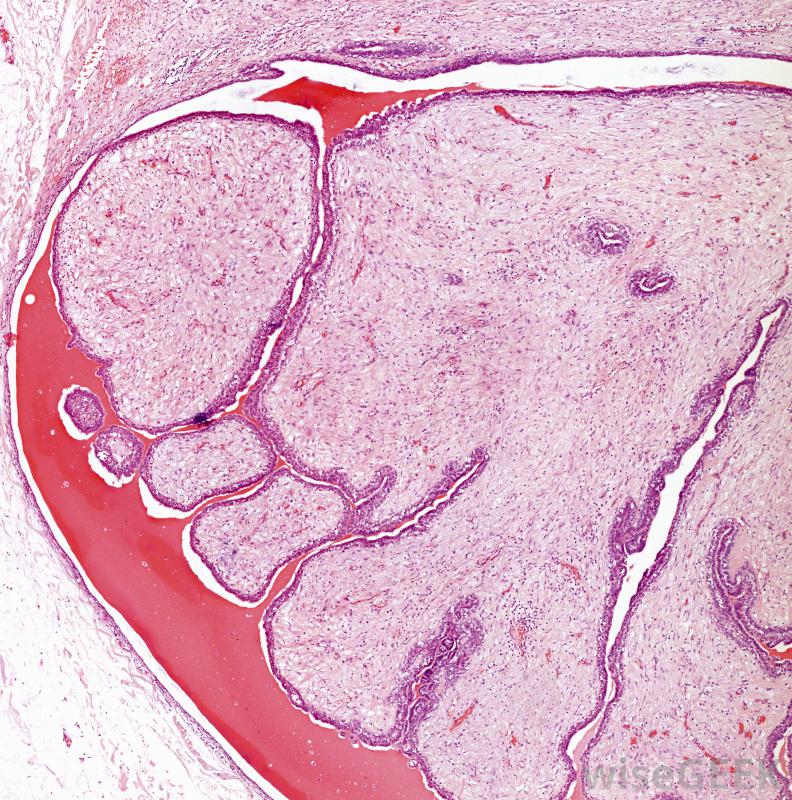

甲状腺低回声肿块的一个例子是良性肿瘤,称为滤泡性腺瘤。令人困惑的是,滤泡性腺瘤也可能出现高回声,其中更多的声波反射回来,呈现出更明亮的外观。无论哪种情况,超声扫描发现的滤泡状腺瘤周围有一个低回声的环。这是最常见的甲状腺肿瘤,通常作为预防措施将其切除,因为有时很难将其与甲状腺癌区分开。